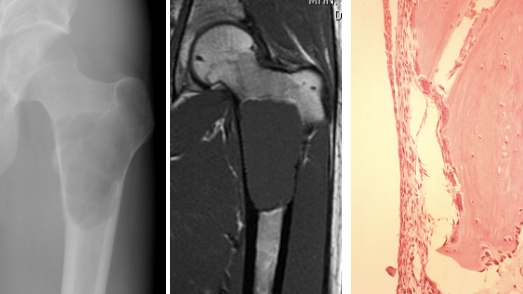

What is seen on radiographs with unicameral bone cysts?

What is seen on histology of unicameral bone cysts?